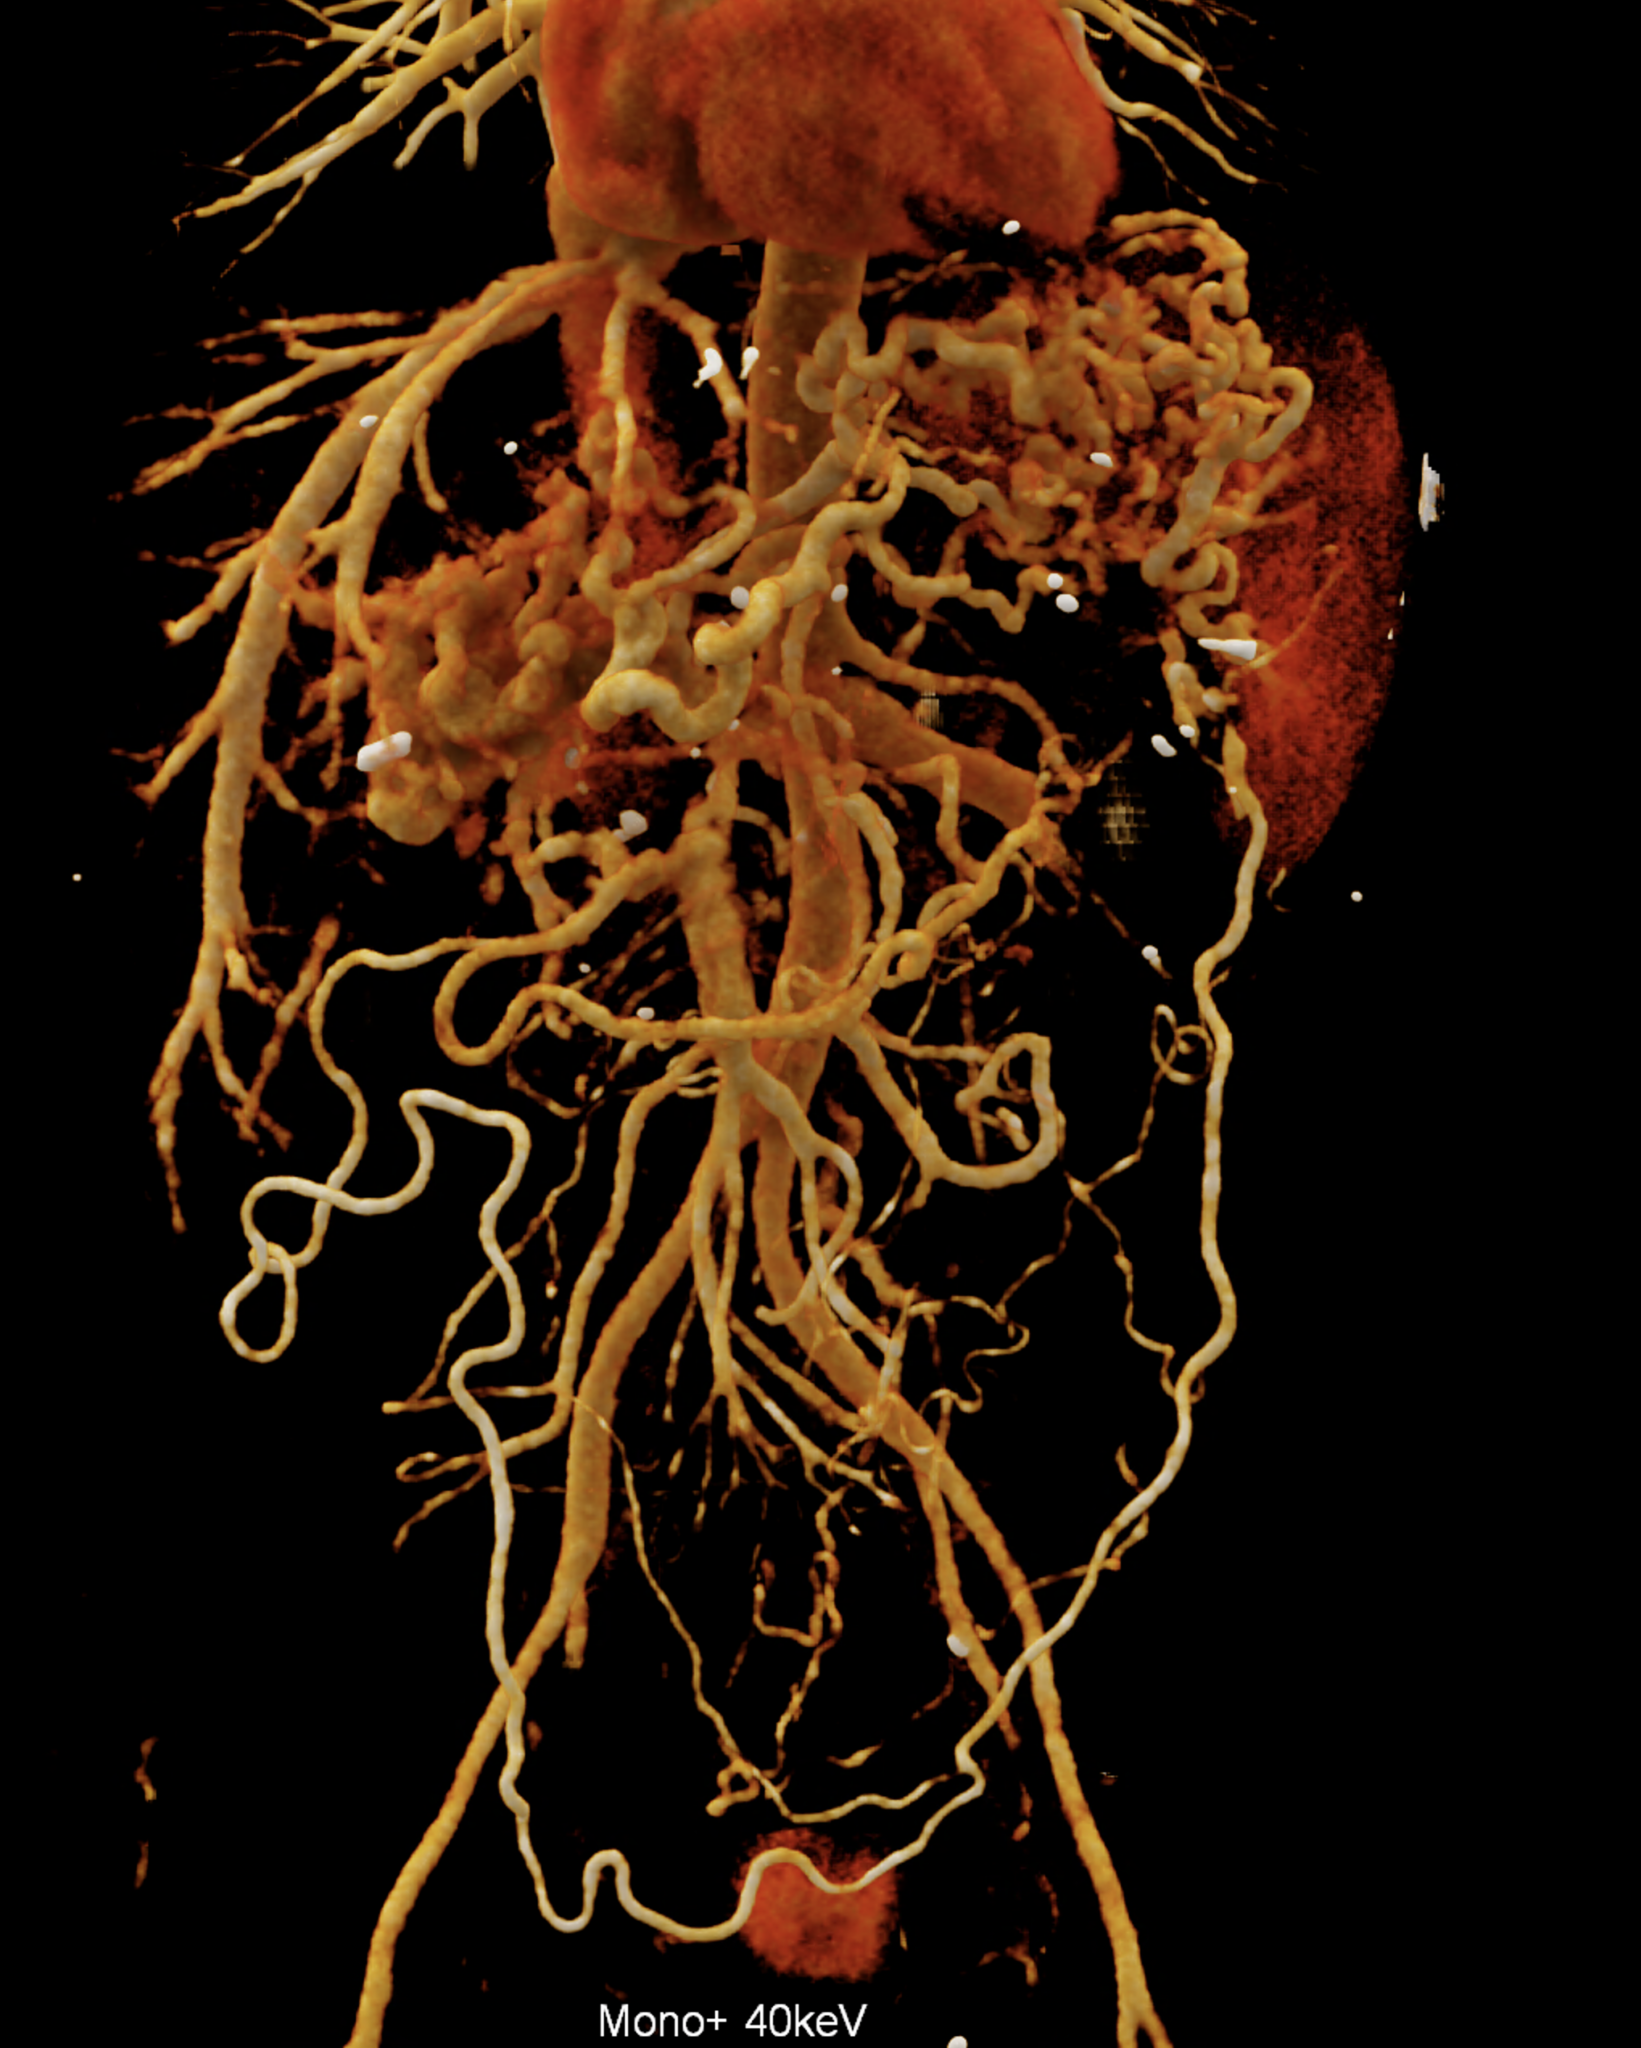

A patient with chronic pancreatitis and chronically occluded portal vein. The bile ducts have a significantly dilated wall, from the trunk, through the stump of the cystic duct, to the right and especially the left branch of the hepatic duct. At the same time, a large pseudocyst in the pancreas, dilatation of the pancreatic duct, and chromic occlusion of the superior mesenteric vein, splenic vein, and portal vein trunk are evident. Along with portal biliopathy, there is also arixy of the cardia and esophagus, as well as cavernous remodeling of the portal circulation itself.

volume rendered image after bone and kidney removal showing best the portal biliopathy